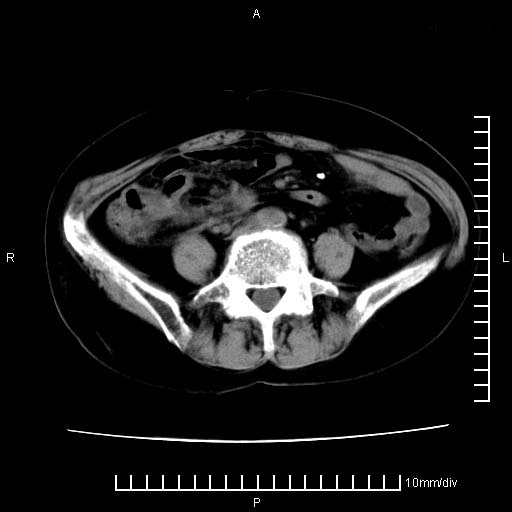

下腹疼痛2月,加重并呕吐2天,下腹压痛,反跳痛。白细胞1万2.

下腹至盆腔较大包块,与邻近肠管关系密切,下腹疼痛2月,加重并呕吐2天,下腹压痛,反跳痛。白细胞1万2.

附件实性肿块有坏死 考虑卵巢癌

来源于附件占位—多考虑:卵巢癌!

不知道大家可要注意下腹腔小肠旁不规则结节状灶,部分钙化,是否要考虑小肠腺癌.盆腔包块可能考虑脓肿.

有病理了,楼上的哥们你说对了

感谢楼主反馈术后病理结果(卵巢癌),学习了!